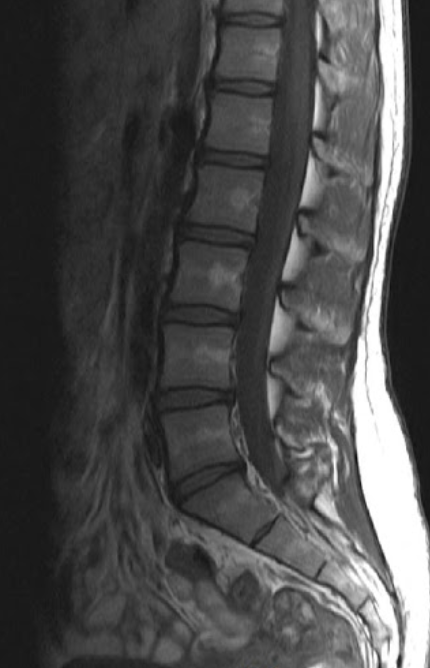

안녕하세요. 오늘은 MRI 건강보험 적용에 대해서 알아보겠습니다. MRI는 꼭필요한 검사이지만 검사비용이 엄청비싸 경제적 부담을 느끼신분들이 많으실겁니다. 하지만 건강보험공단의 보장성 강화에 따라 MRI의 일부 부위에서도 필요시 건강보험 적용이 가능하다고 알려져 있습니다. 저와 함께 하나씩 알아보도록 합시다.

MRI 건강보험 적용